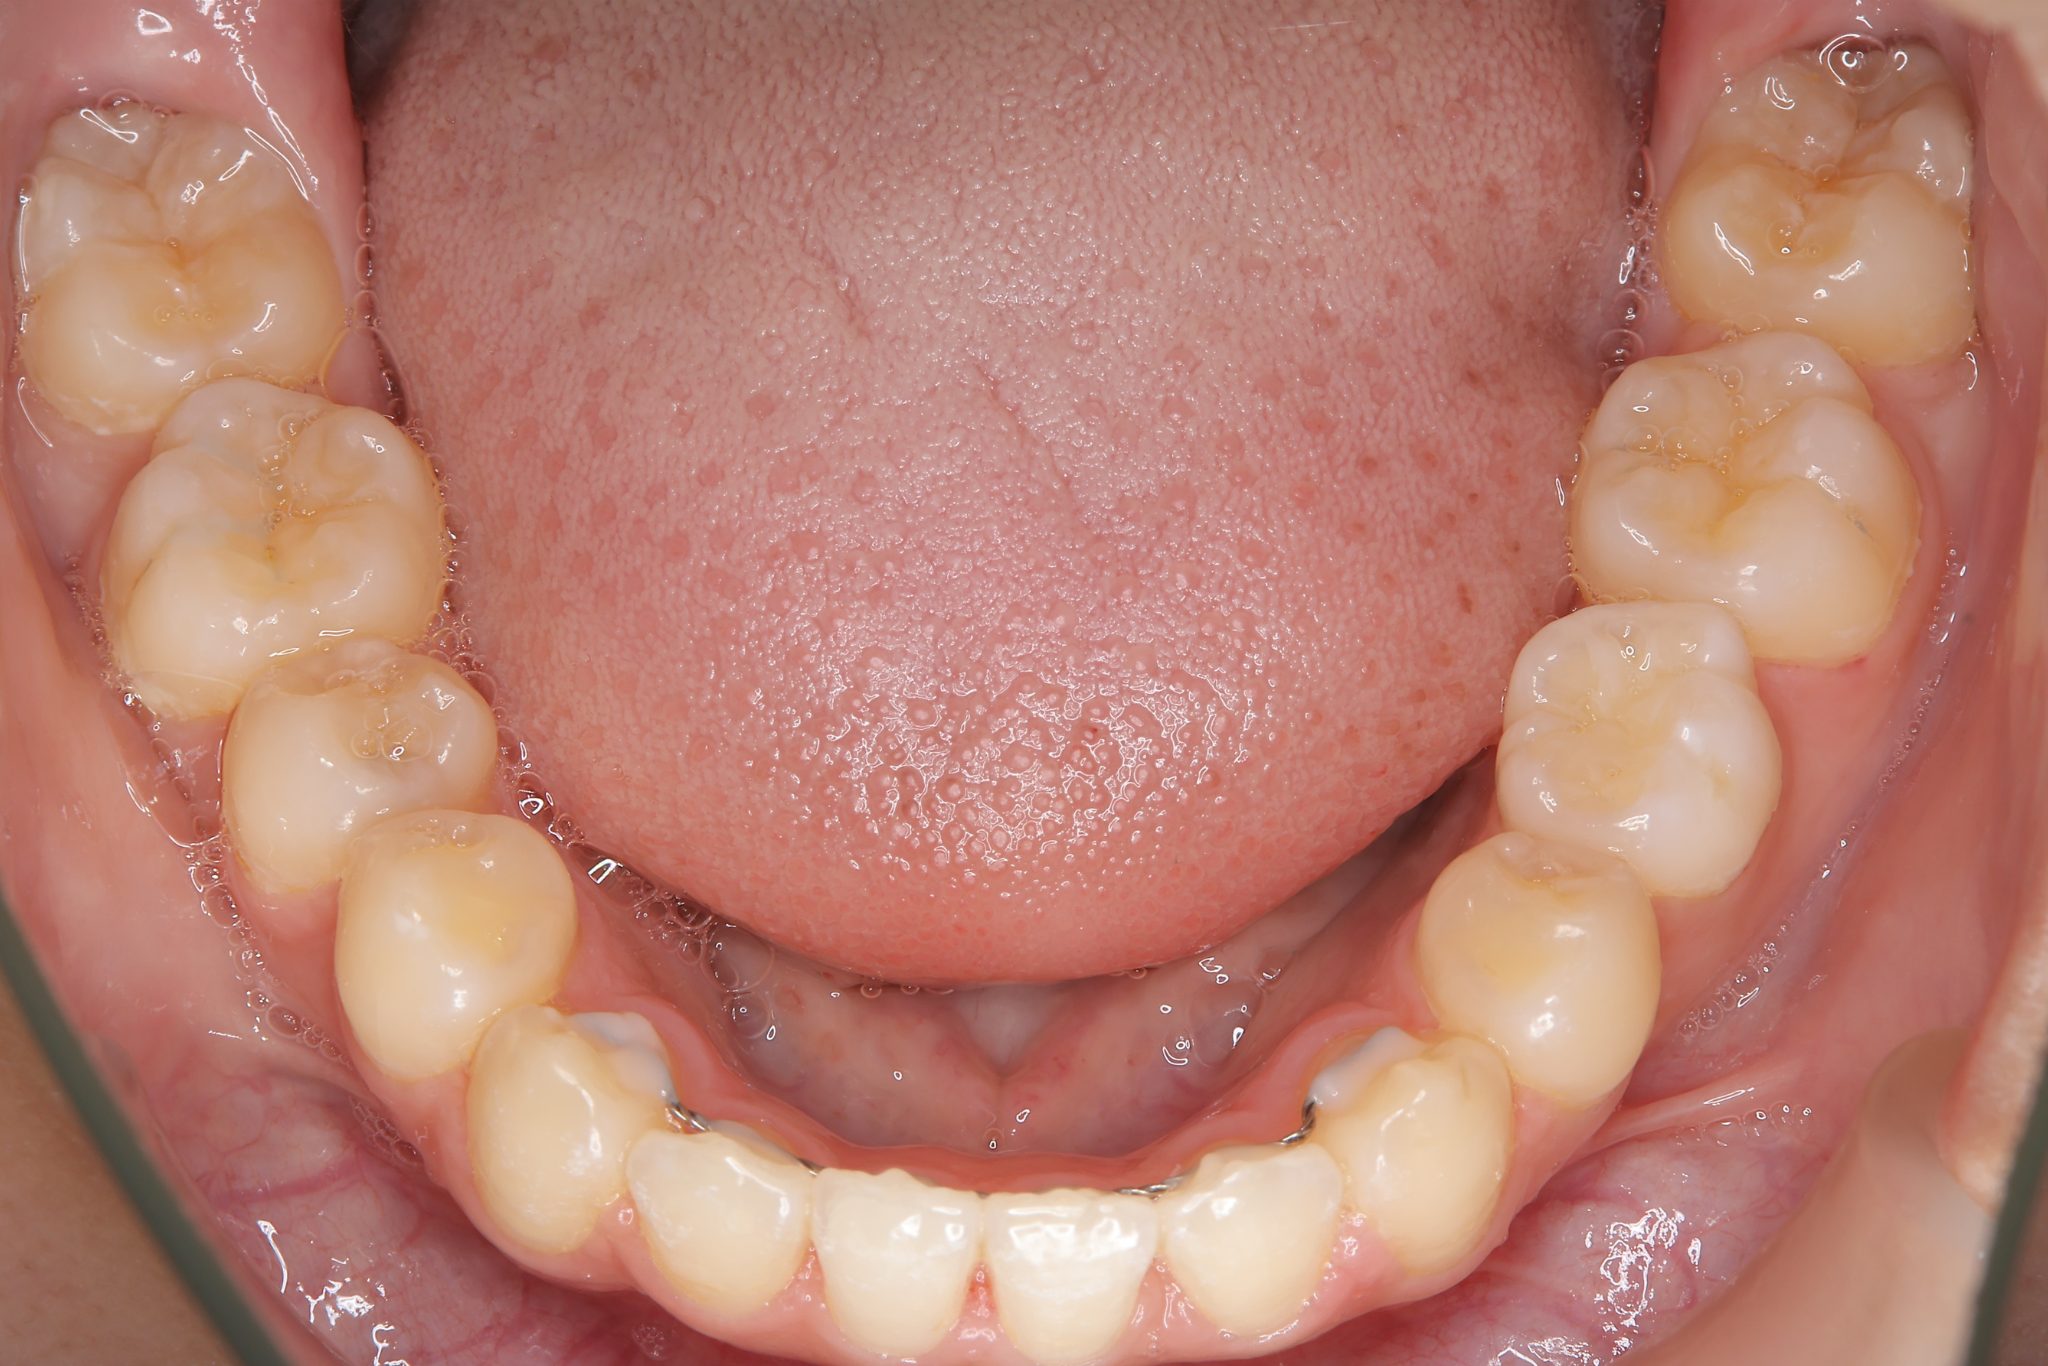

ビフォー

全顎ワイヤー矯正 症例_418

アフター

主訴 歯並びがガタガタ ※抜歯あり

施術内容 成人矯正1期治療

治癒期間 2年10か月間

費用 1,069,200円(税込)